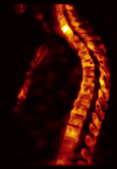

1. Improved imaging results. Through hybrid xSPECT/CT technology, our bone cancer scan is clinically useful compared to SPECT alone because of improved anatomic localisation and diagnostic certainty.

SJMC xSPECT Bone Scan Imaging xSPECT Bone